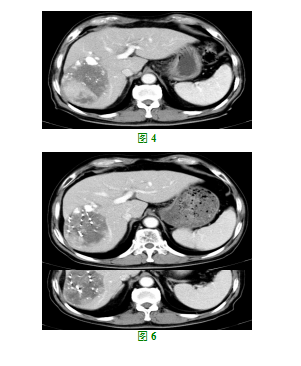

患者,男,70岁,因“乏力、纳差、肝区疼痛4+月”于2017年04月13日入院,患者既往有乙肝病毒携带病史20+年,PS1分,查体:肝脏肋下约3cm,质硬,边缘钝,触痛,肝区叩痛阳性,移动性浊音阴性。入院行上腹部增强CT提示:肝右叶见大小约11.6*8.4cm椭圆形低密度块影,增强扫描亦有强化,块内非均匀性强化,意见:肝硬化,肝右叶块影并强化以肝癌可能。(见图1)AFP9.40ng/mL,血清总胆红素5.3umol/l,血清白蛋白41.4g/l,凝血酶原时间13.7秒,同时完善胸部增强CT,未发现确切肺部转移灶等。根据《原发性肝癌诊疗规范(2017年版)》,有乙型肝炎或丙型肝炎,或者有任何原因引起肝硬化者,对于发现肝内直径>2cm的结节,则动态增强MRI、动态增强CT、超声造影及普美显动态增强MRI四项检查中只要有一项有典型的肝癌特征,即可临床诊断为肝癌[5]。故该患者诊断:原发性巨块型肝癌。Child-Pugh分级A级,因患者肿块很大,且合并肝硬化,经肝胆外科会诊后不建议手术切除,故于2017年4月18日、2017年5月22日行第一次、第二次肝癌TACE治疗,两次介入治疗后复查增强CT(2017.6.26):肝脏外缘凹凸不平,肝脏右叶见大小约11.7*8.7cm团块状影,边界部分不清,其内见部分碘油沉积,肿块大小较前对照未见明显变化,增强后肿块内可见实性成分强化,并见大片坏死灶未见强化。

(见图2),有再次介入治疗指针,于2017年6月27日、2017年8月16日行第三次、第四次肝癌TACE治疗。四次介入结束后,患者于2017年10月23日来院复查增强CT:肝脏外缘凹凸不平,肝脏右叶见大小约9.8*7.0cm团块状影,边界部分不清,其内见部分碘油沉积,肿块大小较前对照略有缩小,增强后肿块内可见实性成分强化,并见大片坏死灶未见强化。肝左叶散在分布多个0.3-0.6cm低密度无明显强化结节影,部分系囊肿,部分性质待定。(见图3),AFP6.90ng/mL。患者目前肿瘤无增大,无解剖性肝叶切除指针,目前肿瘤区碘油沉积情况尚可,但肝左叶有散在结节,不排除肿瘤肝内转移可能,目前无继续介入治疗指针。结合我国自主研发的抗血管生成靶向药物甲磺酸阿帕替尼的临床研究,该药与治疗肝癌的甲苯磺酸索拉菲尼片作用机理类似,且有大量的临床数据支持在肝癌方面的应用,在充分征求患者及家属同意的情况下,于2017年10月25日开始口服艾坦(甲磺酸阿帕替尼)250mg po qd治疗,治疗期间患者出现尿蛋白++,血压增高,给予降血压治疗后恢复,治疗1月后于2017年11月27日行增强CT:较2017年10月23日CT片对照,肝脏肿块未见明显变化,肝左叶散在分布多个0.3-0.6cm低密度无明显强化结节影,部分系囊肿,部分性质待定。较前未见变化,随访。AFP4.90ng/mL。临床疗效评价为SD。继续口服该药。2018年01月08日行增强CT:肝脏外缘凹凸不平,肝脏右叶团块状影大小约10*7.0cm,边界部分不清,其内见部分碘油沉积,增强后肿块内可见实性成分强化,并见大片坏死灶未见强化。(见图4),患者肿瘤稍缩小,未达到PR,且一直有强化,肿瘤供血,经全科讨论后,制定B-TPS计划,于2018年01月23在CT引导下行放射性碘125粒子植入治疗,共植入碘125粒子30粒,肿瘤周边剂量为140Gy,粒子表面活度为0.8mCi。2018年02月27日复查增强CT提示为SD,故于2018年03月07日再次在CT引导下行放射性碘125粒子植入治疗,再次植入碘125粒子30粒,肿瘤周边剂量为140Gy,粒子表面活度为0.8mCi。患者继续口服艾坦,2018年07月02日复查增强CT:肝脏外缘僵硬,凹凸不平,肝右叶低密度影,大小约6.4*6.0cm,增强边缘显示清楚,动脉期见片状强化,静脉期亦见明显片状强化。提示部分肿瘤仍存在动脉供血。(见图5),临床疗效评价为PR。结合患者现在的情况,我们又组织科内讨论,于2018年07月20日又行TACE治疗一次,经上述治疗后患者继续口服艾坦治疗,至2018年12月03日复查增强CT临床疗效评价为SD。(见图6),患者一般状况佳,PS评分0分,无肝区疼痛等不适,肝功能正常。继续口服艾坦治疗中。